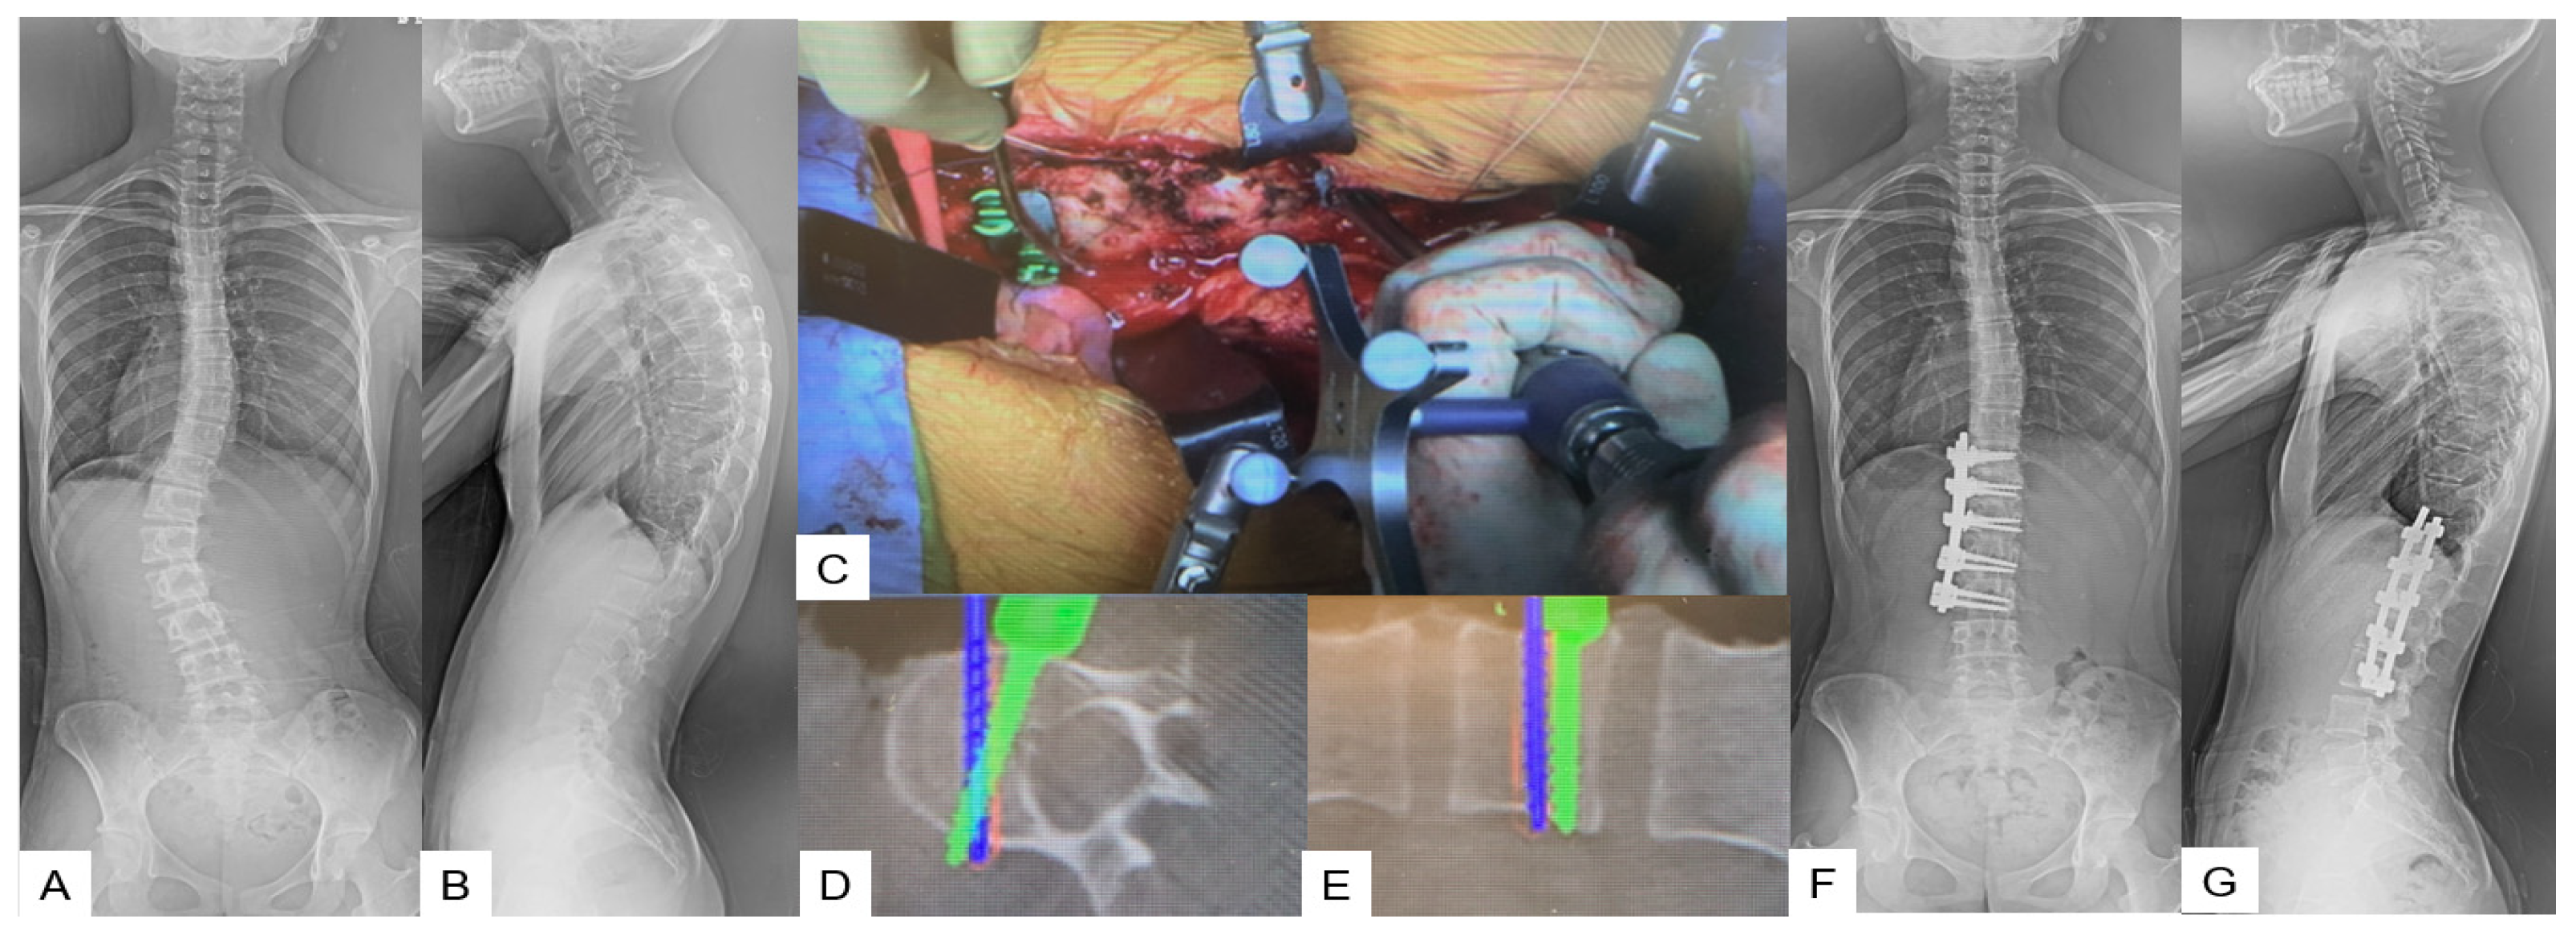

Anterior Correction for Lenke Type 5